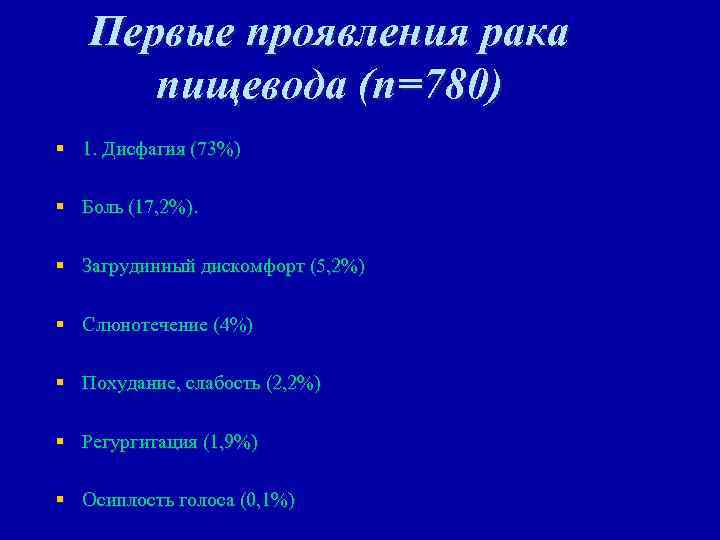

Первые проявления рака пищевода (n=780) § 1. Дисфагия (73%) § Боль (17, 2%). § Загрудинный дискомфорт (5, 2%) § Слюнотечение (4%) § Похудание, слабость (2, 2%) § Регургитация (1, 9%) § Осиплость голоса (0, 1%)